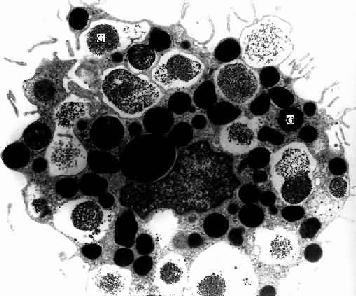

2.巨噬细胞 巨噬细胞(macrophage)是体内广泛存在的具有强大吞噬功能的细胞。在疏松结缔组织内的巨噬细胞又称为组织细胞(histiocyte),常沿纤维散在分布,在炎症和异物等刺激下活化成游走的巨噬细胞。巨噬细胞形态多样,随功能状态而改变,通常有钝圆形突起,功能活跃者,常伸出较长的伪足而形态不规则。胞核较小,卵圆形或肾形,多为偏心位,着色深,核仁不明显,胞质丰富,多呈嗜酸性,含空泡和异物颗粒,电镜下,细胞表面有许多皱褶、小泡和微绒毛,胞质内含大量初级溶酶体、次级溶酶体、吞噬体、吞饮小泡和残余体。细胞膜附近有较多的微丝和微管(图3-5,3-6)。

图3-6 猴巨噬细胞电镜像×8400

(白求恩医科大学尹昕、朱秀雄教授供图)

巨噬细胞是由血液内单核细胞穿出血管后分化而成。此时,细胞变大,线粒体及溶酶体增多,粘附和吞噬能力增强。在不同组织器官内的巨噬细胞存活时间不同,一般为2个月或更长。

巨噬细胞有重要的防御功能,它具有趋化性定向运动、吞噬和清除异物及衰老伤亡的细胞、分泌多种生物活性物质以及参与和调节人体免疫应答等功能。